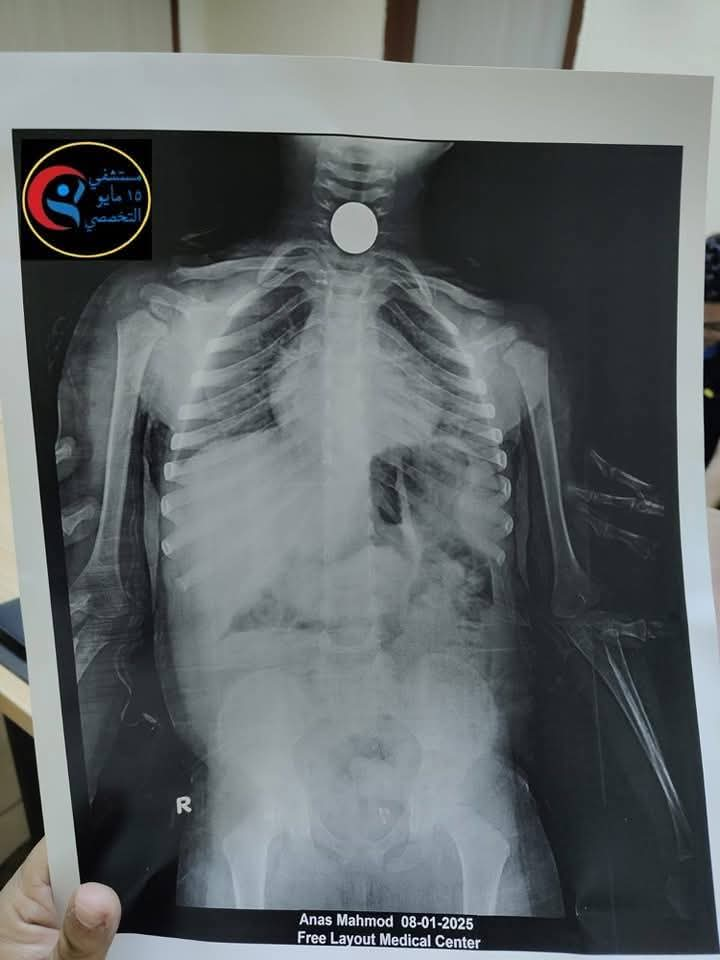

أكد مستشفي ١٥ مايو النموذجي أنه تم التعامل مع الحالة بسرعة كبيرة، حيث أجريت الأشعة اللازمة ، وتبين وجود الجسم الغريب أسفل الصمام العلوي للمريء.

وقد تم تجهيز الطفل ودخوله العمليات لاستخراج الجسم الغريب باستخدام المنظار تحت التخدير العام، وتم استخراج العملة المعدنية بنجاح.